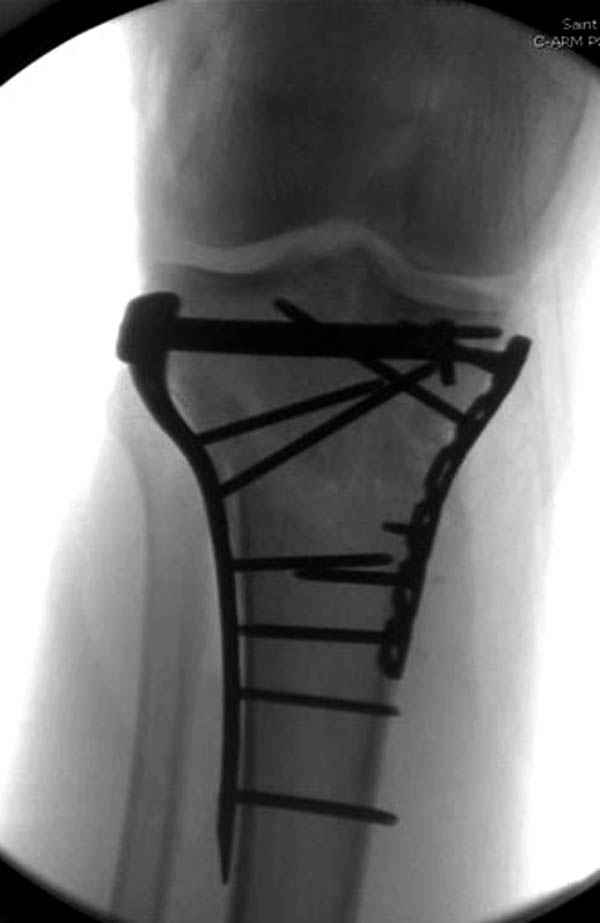

Пациенту сделали КТ - ухитрились сделать на шине Белера (не давал положить прямую ногу) - срезали передний отдел. Планируется на пятницу (24.12) на операцию - синтез длинной мыщелковой LCP-пластиной Synthes :). Отек ближе к слову умеренный (окружность голени +4 см по сравнению со здоровой). КТ и снимок на вытяжении прилагаются.

Уважаемые коллеги! В прошлую пятницу больной прооперирован - как и планировалось мыщелковая LCP от ChM. Малоинвазивно не получилось - один большой доступ :(. (но с минимальным скелетированием б/б кости). Наружный мыщелок собрали, но по контролю видно, что задне-медиальный отдел метаэпифиза смещен. Фиксировать не стали (?). 4-е сутки после операции - по м/тканям без проблем. Дополнительная иммобилизация синтетическим тутором.

P. S. перелом диафиза на контроле не совсем захвачен, но проблем там нет. Приношу извинения за низкое качество Р-грамм - выполнены на сканере (фотоаппарат не работает :)) .

Трудно поверить, что разрекламированная Ортопедическая школа Восточной Украины позволяет такие странные снимки? На прямом снимке сохранен общий контур плато, но не известна судьба импрессии суставной поверхности. На полубоковой?, оставлен без репозиции задне-медиальный отдел, и навряд ли после такой фиксации можно удовлетвориться результатом.

Такая ситуация характерна для многих, когда принимается ошибочное решение, т.е пытаются фиксировать одним имплантом переломы двух мыщелков. Латеральная пластина приемлема только для тех случаев, когда сохраняется интактным медиальный диафизарный кортекс и отсутствует фрагментация на верхушке медиального перелома.

Здесь как раз тот случай, когда результат зависит не только от мастерства хирурга, но и от наличия современных методов исследования. Например, КТ которая поможет рассчитать направления шурупов и установку импланта. Кроме этого, поможет определиться с доступом.

На представленных предоперационных срезах КТ огромный задне-медиальный фрагмент расположен больше кзади, чем медиально. Для планирования, кроме поперечных срезов, надо ориентироваться на корональные срезы, которые укажут топографию верхушки медиального фрагмента.